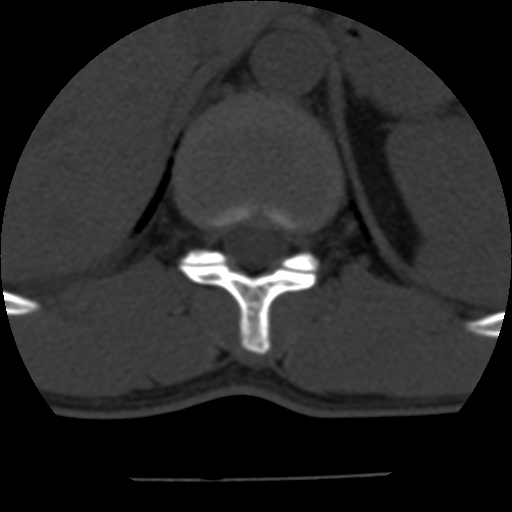

男,31岁,从6米高处坠落伤两天,腰背部疼痛,临床要求ct扫描胸10-腰1。请大家帮忙看看骨质有问题吗?

t12、l1锥体前缘轻度楔形变,平扫示椎体前缘骨小梁欠规整,第9幅图示椎体前缘骨质不连续,结合外伤史考虑椎体轻度压缩骨折。

楼主扫描层厚可能较大,每个椎体只有三个层面.

从所示层面分析,无明确骨折征象,象类似病人我个人会建议mri除外骨挫伤.